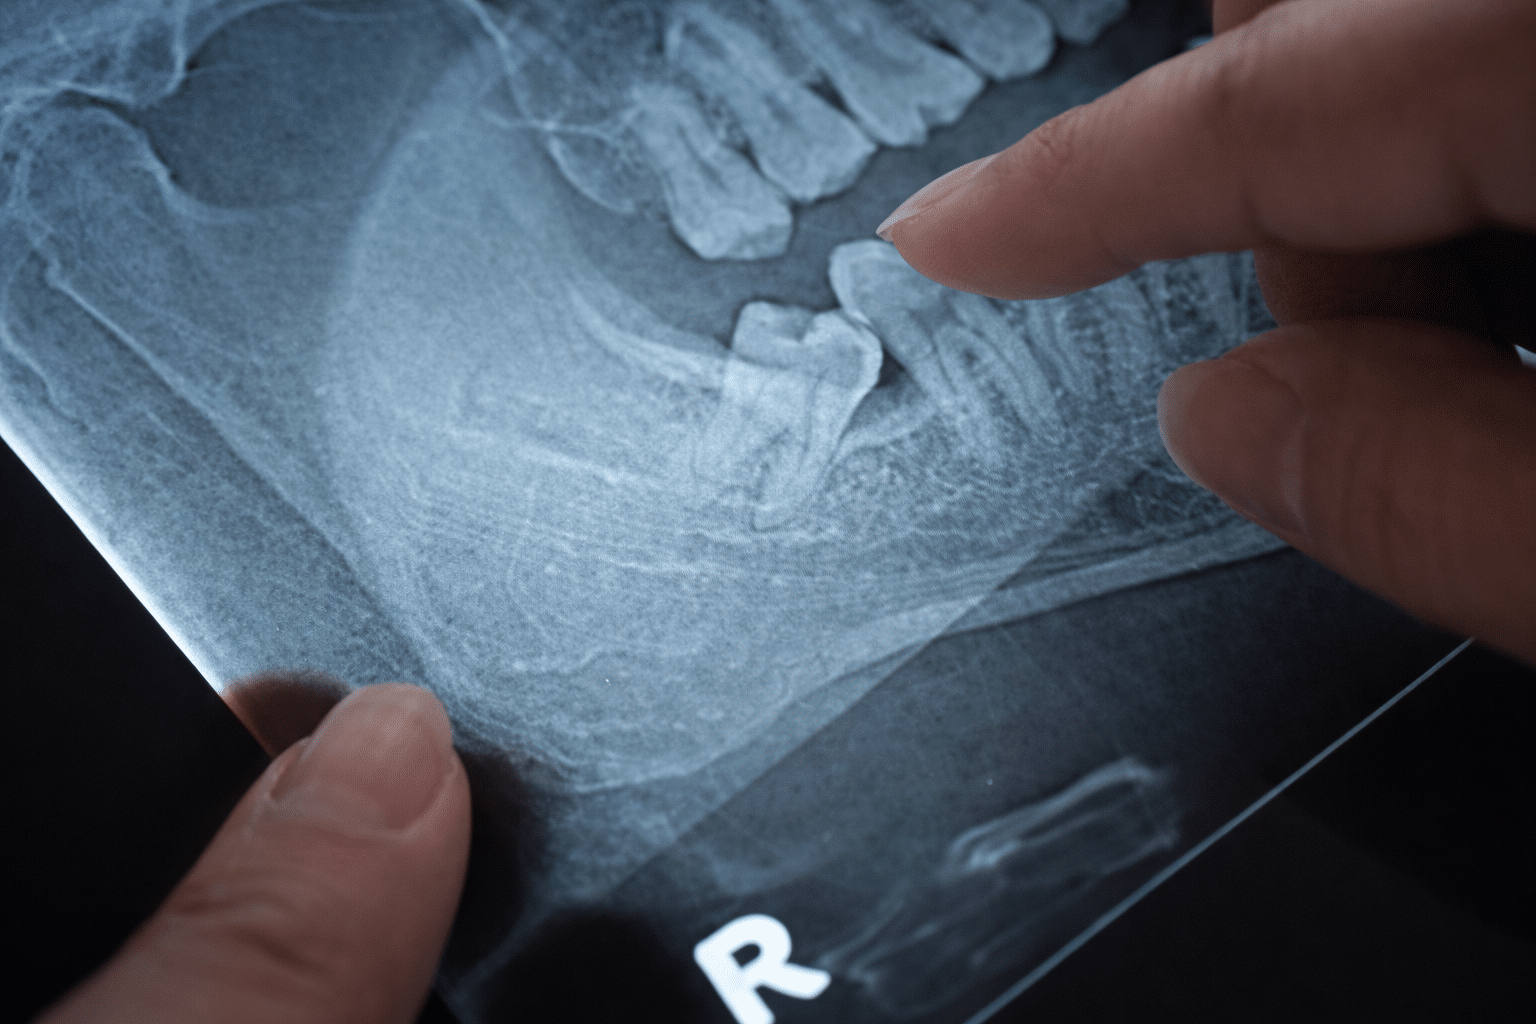

In many situations, your general dentist may recommend early assessment or preventative removal, especially if X-rays show that the teeth are impacted or likely to cause issues later.

Your dentist will assess whether early removal is appropriate based on clinical examination and X-rays.

However, only a dental examination and X-ray can confirm this. Proactive evaluation helps prevent unexpected pain and complications later on.